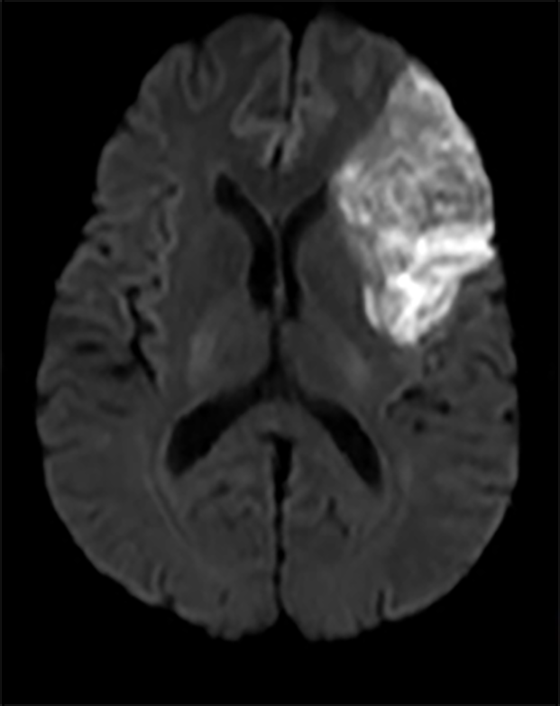

Deși unele tipuri de infarct sunt aparente pentru ochiul liber neprofesionist (Fig.2), altele sunt mai subtile și mult mai reduse în intensitatea aparentă și dimensiune (Fig.3 & Fig.4).

Fig. 2 a) Simulare detecție de infarct cerebral acut din RMN-DWI. Ref: [6]